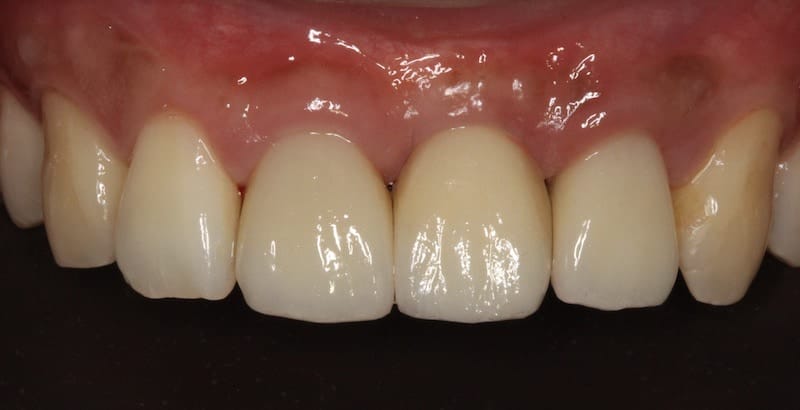

最終,我們以三顆全瓷冠假牙修復完成。我們確實也達到我們所設定的目標:在牙齒的顏色、長度寬度、牙齒之間和牙齦高度的協調性都很高。也相信 Mr.Wang 有了兼具功能、美觀的牙齒,一定更能展現充滿自信的笑容。

完成人工植牙後,與桃園全瓷美學專家沈志容醫師合作,以數位全瓷冠修復三顆前牙 完成的全瓷冠牙套顏色、細節逼真,前牙咬合時幾乎看不出差異

圖示:人工植牙手術前後X光片比較:(左)假牙拆除後,可見缺牙處兩邊的支柱牙結構破壞嚴重;(右)人工植牙手術後,完成全瓷冠假牙